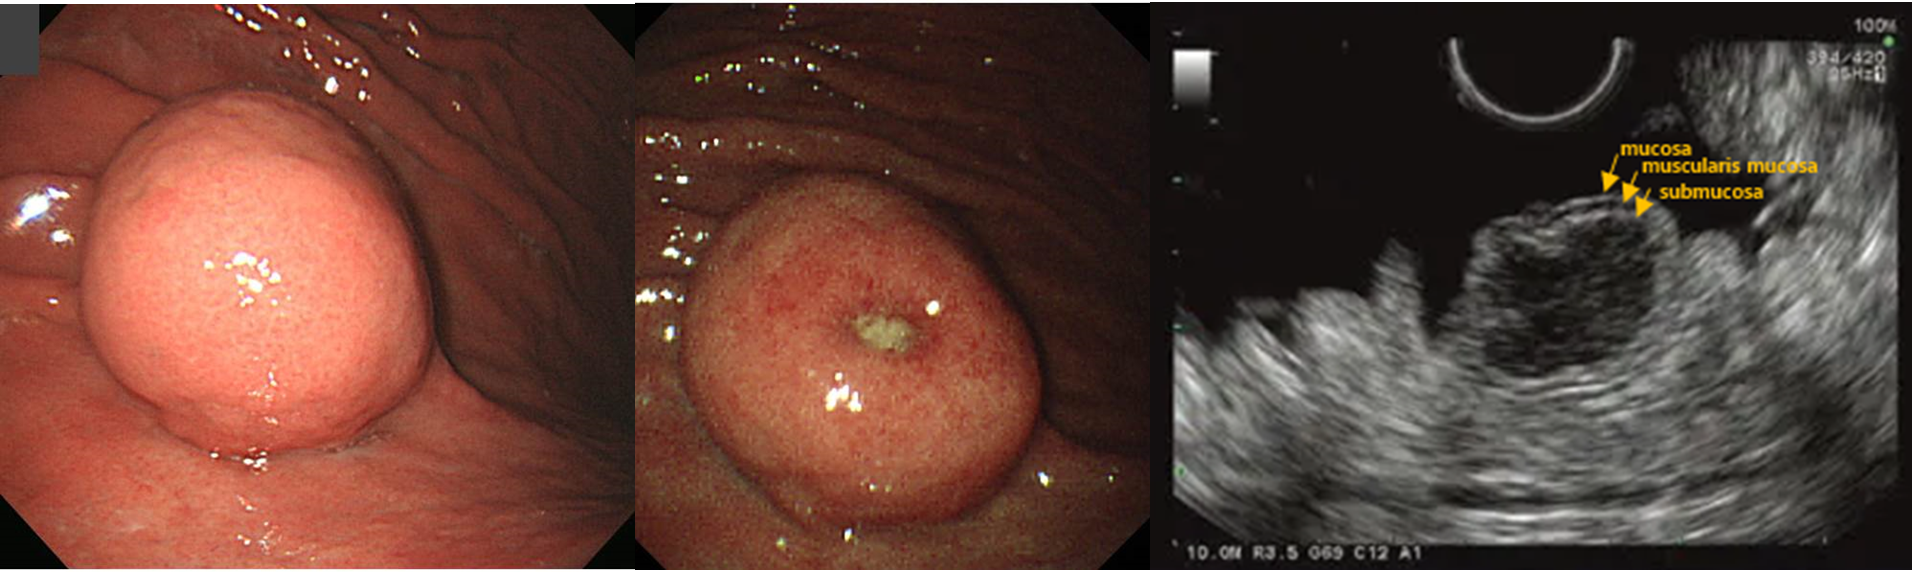

• 위내시경, 내시경 초음파

** 위내시경: nonspecific smooth bulging mass covered by normal mucosa